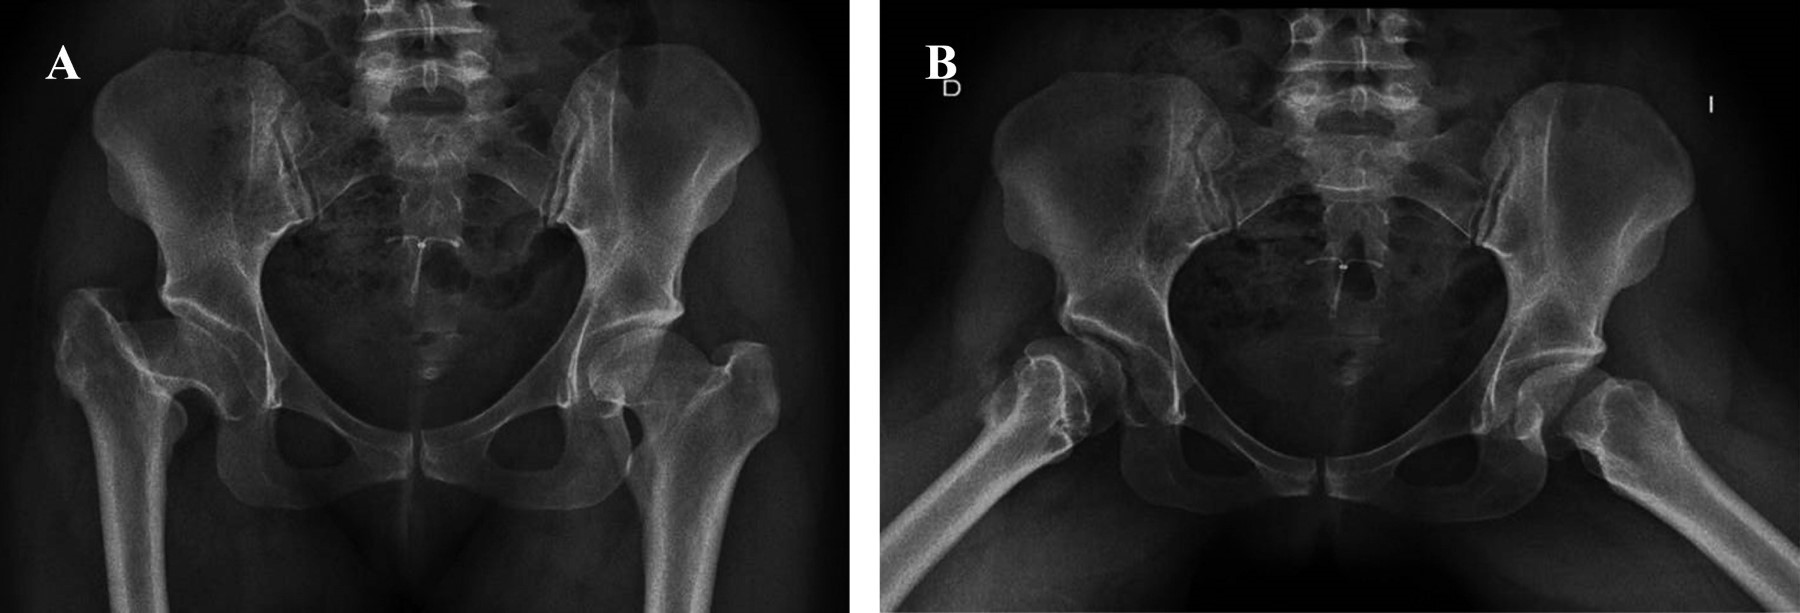

Las secuencias están ilustradas en las Figuras 1, 2, 3, 4, 5, 6 y 7.

EVALUACIÓN RADIOGRÁFICA

La anteversión acetabular tuvo un promedio de 10° (IQR 0°-15°), no observándose componentes acetabulares retroversos. El ángulo de inclinación tuvo una mediana de 43° (rango intercuartílico [RIC]: 38° a 51°). En dos (9.9%) pacientes se detectaron líneas radiolúcidas sin progresión o significancia clínica; el resto de los sujetos presentaron cinco de los signos radiográficos de Moore para osteointegración del cotilo. En 20 pacientes (90.1% de la serie), la medición postoperatoria de la longitud de los miembros no encontró discrepancia entre el operado y el contralateral, en un caso se presentó una hipermetría menor a 0.5 cm y una hipermetría entre 0.5 a 1 cm. En ningún caso hubo disconformidad con el resultado funcional. Se detectó la aparición de calcificaciones heterotópicas de tipo 1 (clasificación de Brooker) en dos casos, sin ninguna relevancia clínica.

Figura 5

Figura 6